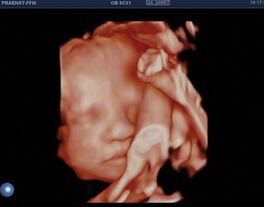

Ersttrimesterscreening (Nackenfaltenmessung)

Diese „erste“ große Untersuchung kann in der Schwangerschaftswoche (SSW) 11+ 0 bis 13+ 6 durchgeführt werden.

Der Ursprung dieser Untersuchung, die Nackenfaltenmessung zusammen mit bestimmten Hormonwerten aus den mütterlichen Blut, zielte hauptsächlich auf eine Risikoabschätzung für das Vorliegen einer genetischen Veränderung des Kindes ab. Mittlerweile können mit dieser Methode viele zusätzliche Risiken für die werdende Mutter und das Kind abgeschätzt werden.

Das Ersttrimesterscreening wird bei uns standardmäßig mit der Untersuchung des fetalen Nasenbeins, mit dem Zufluß zum fetalen Herzen (Ductus venosus), einer frühen Beurteilung des fetalen Herzen, der frühen Beurteilung des fetalen Gehirns (ZNS) und mit den zuführenden Gefäßen zur Gebärmutter (Aa. uterinae) durchgeführt.